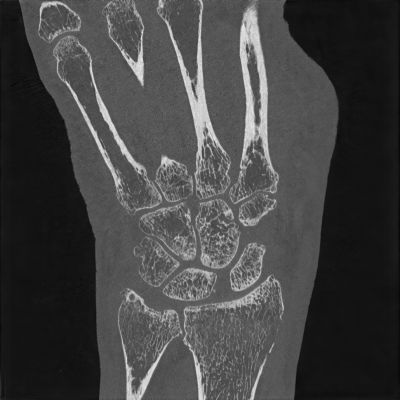

Handgelenk

Beim Gelenken sind mit dem Photon-Counting-CT Darstellungen von feinsten Strukturen möglich.